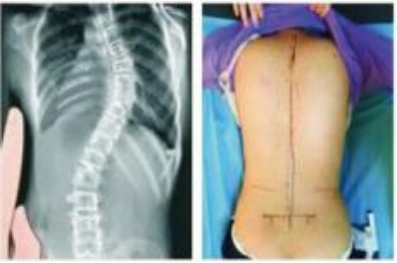

住院过程中最温暖人心的是彼此的信任和理解,所以飞飞经过不到1个月的治疗身体已经有了明显的改善,两侧腰背部平整度明显恢复,肌肉僵硬状态已好转,复查X线显示:脊柱基本居中,病情好转,予以出院。

治疗前后对比图: